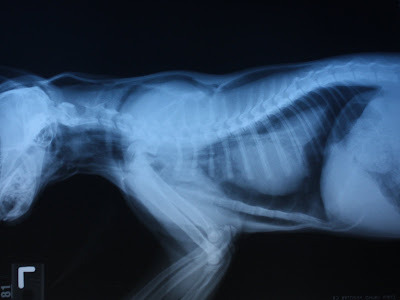

The kitten's heart should be in contact with his sternum (breastbone.) Instead, it is elevated, lifted up by an accumulation of air in the chest cavity. One lung is all black, filled with air, while the other is much smaller and gray in color. That lung has collapsed.

Pneumothorax

| (A) Mediastinal shift observed on the 15th postoperative day on a ventrodorsal radiograph of a dog with right pneumonectomy. h: heart. (B) This postmortem ventro-dorsal radiograph shows tension pneumothorax and subcutaneous emphysema (arrow) in a dog with BPF. |